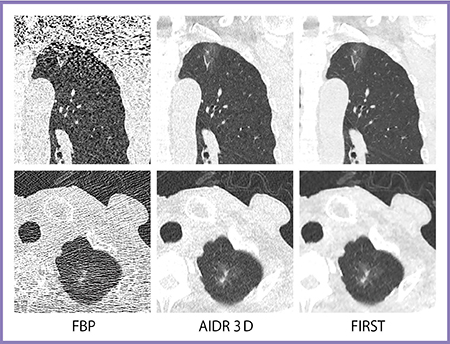

前述の通り,FIRSTでは肺がん検診用の低線量(2mSv)撮影でも,ノイズが少ない非常に明瞭な画像を得られる。超低線量(0.2mSv)撮影の場合,FBPでは肺尖部はノイズが多く評価できないが,FIRSTでは非常に淡いすりガラス状陰影も明瞭に描出できる(図6)。

図6 肺がん検診用超低線量胸部CT(0.2mSv)